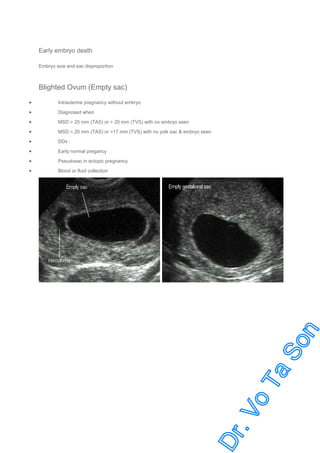

Early embryo death

Embryo size and sac disproportion

Blighted Ovum (Empty sac)

Intrauterine pregnancy without embryo

Diagnosed when

MSD > 25 mm (TAS) or > 20 mm (TVS) with no embryo seen

MSD > 20 mm (TAS) or >17 mm (TVS) with no yolk sac & embryo seen

DDx :

Early normal pregancy

Pseudosac in ectopic pregnancy

Blood or fluid collection

Blighted ovum

Gestational sac without embryo, subcorion hematoma

Gestational sac without embryo,

Aborted sac: placenta and sac without embryo